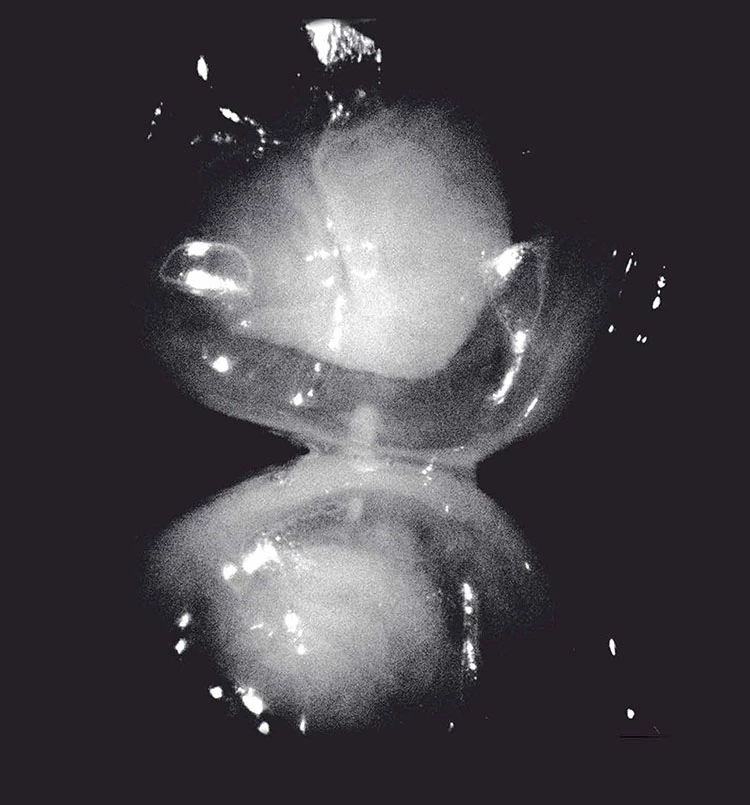

Mit dem Proxi-Wechselkopf der Intraoralkamera kann eine Approximalkaries frühzeitig erkannt werden, ohne den Patienten einer Strahlenbelastung auszusetzen. Mit 2 integrierten Infrarot-LEDs werden z.B. 2 benachbarte Zähne angestrahlt. Der Zahnschmelz im Approximalraum erscheint im Infrarotlicht leicht transparent. Gesunder Zahnschmelz ist für Licht im infraroten Spektrum durchlässig und wirkt dabei dunkel (transparent). Kariesläsionen dagegen erscheinen aufgrund der veränderten Materialstruktur weiß-opak. Somit kann der Behandler die Therapie festlegen und darüber hinaus die erstellten Aufnahmen in HD-Qualität bereits am Monitor für ein Patientengespräch heranziehen (Abb. 1 und 2).